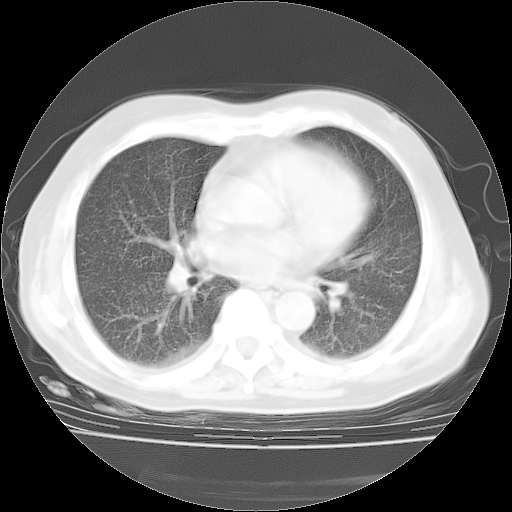

今天部分检查

轻微咳嗽,无痰,(体温正常时)R20次/分,P75次/分,双肺底、腋下可闻及少量捻发音。下肢轻度浮肿。

腹部B超:胆囊壁增厚,肝、胆、胰、脾、肾无异常,肠系膜淋巴结、腹膜后淋巴结无增大。

ECG:右心室增大

心脏超声检查:无右心室增大。